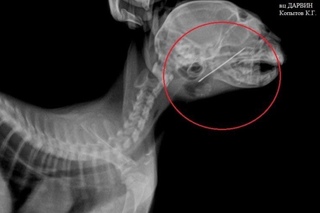

Особую проблему представляет собой хирургия пищевода грудного отдела. Операция проходит в грудной полости в условиях искусственной вентиляции лёгких. Для проведения подобного оперативного вмешательства необходимо чётко знать местоположение инородного тела в пищеводе, так как разное положение определяет место доступа в грудную полость. Для этого необходимо провести эзофагогастроскопию животному (фото 4,5,6,7).

Фото 4а, 4б, 4в: Кость в пищеводе грудной части у йоркширского терьера

На фото 5а, 5б, 5в: Кость в пищеводе грудной части у грифона